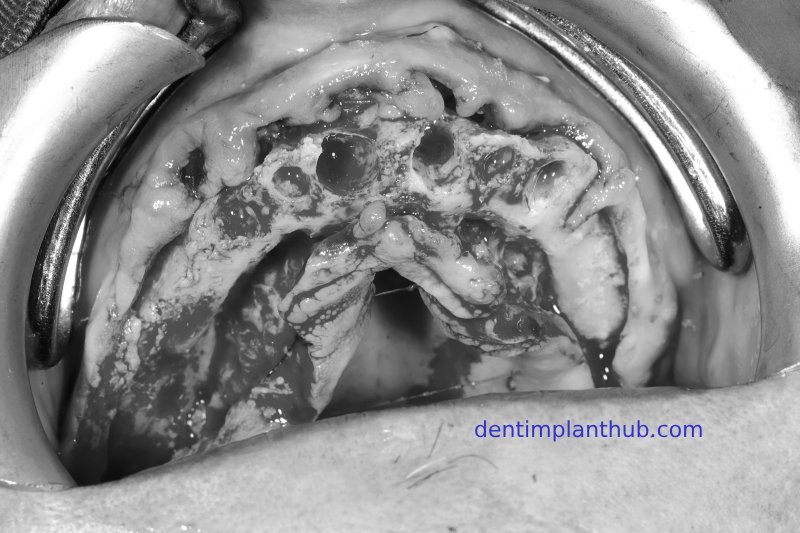

The patient's intra - oral photos before the surgery

The specific details of the implant surgery

The surgery was conducted on Wednesday, August 3rd, 2022, at 8:30 a.m. - For tooth 12, the implant model is 3612. - For tooth 14, the implant model is 4010, with 1 pack (0.25 grams) of bone powder and 1 piece of collagen sponge. - For tooth 18, the implant model is 4510, implanted at an inclination. - For tooth 22, the implant model is 3612. - For tooth 24, the implant model is 4010. - For tooth 26, the implant model is 5010, with internal maxillary sinus lift, and 1 pack (0.25 grams) of bone powder. - For tooth 45, the implant model is 4510. - For tooth 46, the implant model is 4510. - For tooth 36, the implant model is 4510, with immediate implant placement, and 1 pack (0.25 grams) of bone powder.

Photos taken during the implant surgery